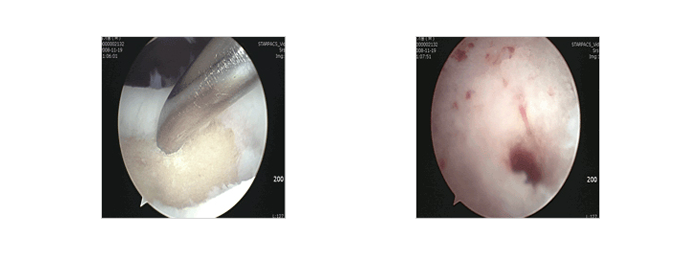

골수 자극법 - 천공술, 미세 골절술 - 사진

자가 골연골 이식술

자가 골연골 이식술 - 사진